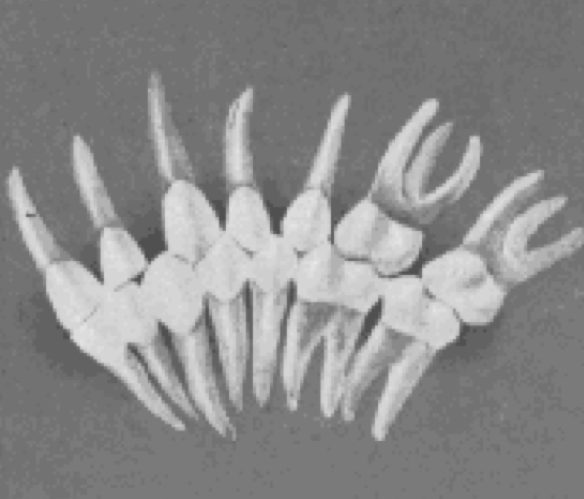

Crown angulation (tip)

Distal than incisal

gingival portion of the long axes of all crowns was more…

angle between the long axis of the crown and a line bearing 90 degress from the occlusal plane

Plus reading

gingival portion of the long axis of all crown is distal to the incisal portion

Minus reading

gingival portion of the long axis of the crown is mesial to the incisal portion